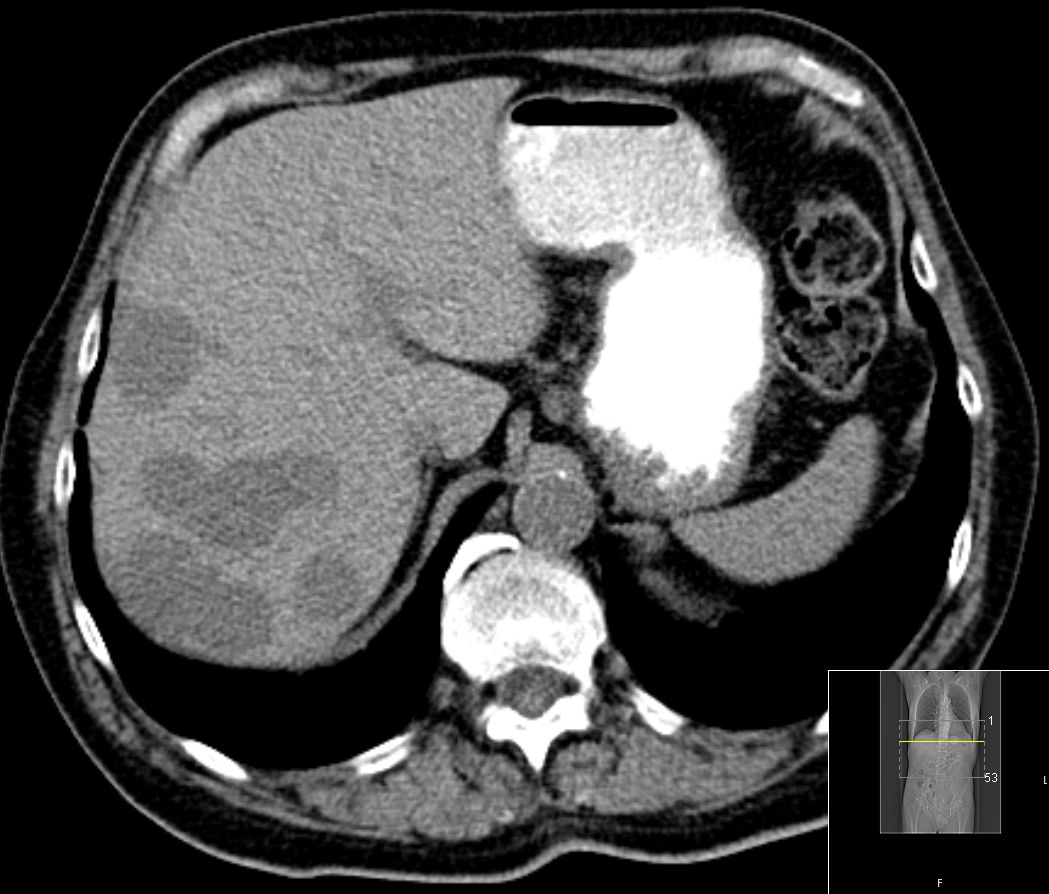

| CT | 57-jähriger Mann mit einem pulmonal und

hepatisch metastasierten Rektumkarzinom. Progress unter Chemotherapie.  | 48-jähriger Mann mit Lebermetastasen nach

| CT | 75-jähriger Mann, der vor einem Jahr ein Rektum-Karzinom hatte: ypT3a ypN1b(2/18) Mo Li Vo G2. 5x5Gy.

Anteriore Rektumresektion, 4x 5-FU. Jetzt Lebermetastasen.  |  |  |  |